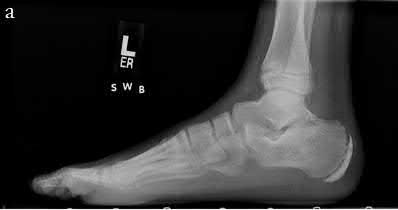

A 28-year-old male sustained a displaced talar neck fracture and underwent open reduction and internal fixation.

Six weeks postoperatively, a subchondral radiolucent band is seen in the talar dome on the AP mortise radiograph. What does this radiographic finding indicate?

Explanation

Hawkins sign is a subchondral radiolucent band seen in the talar dome 6 to 8 weeks after a talus fracture. It represents subchondral osteopenia secondary to disuse atrophy. Because bone resorption requires an active blood supply, the presence of a Hawkins sign is a highly reliable indicator that the talar body has intact vascularity and that avascular necrosis (AVN) is unlikely.